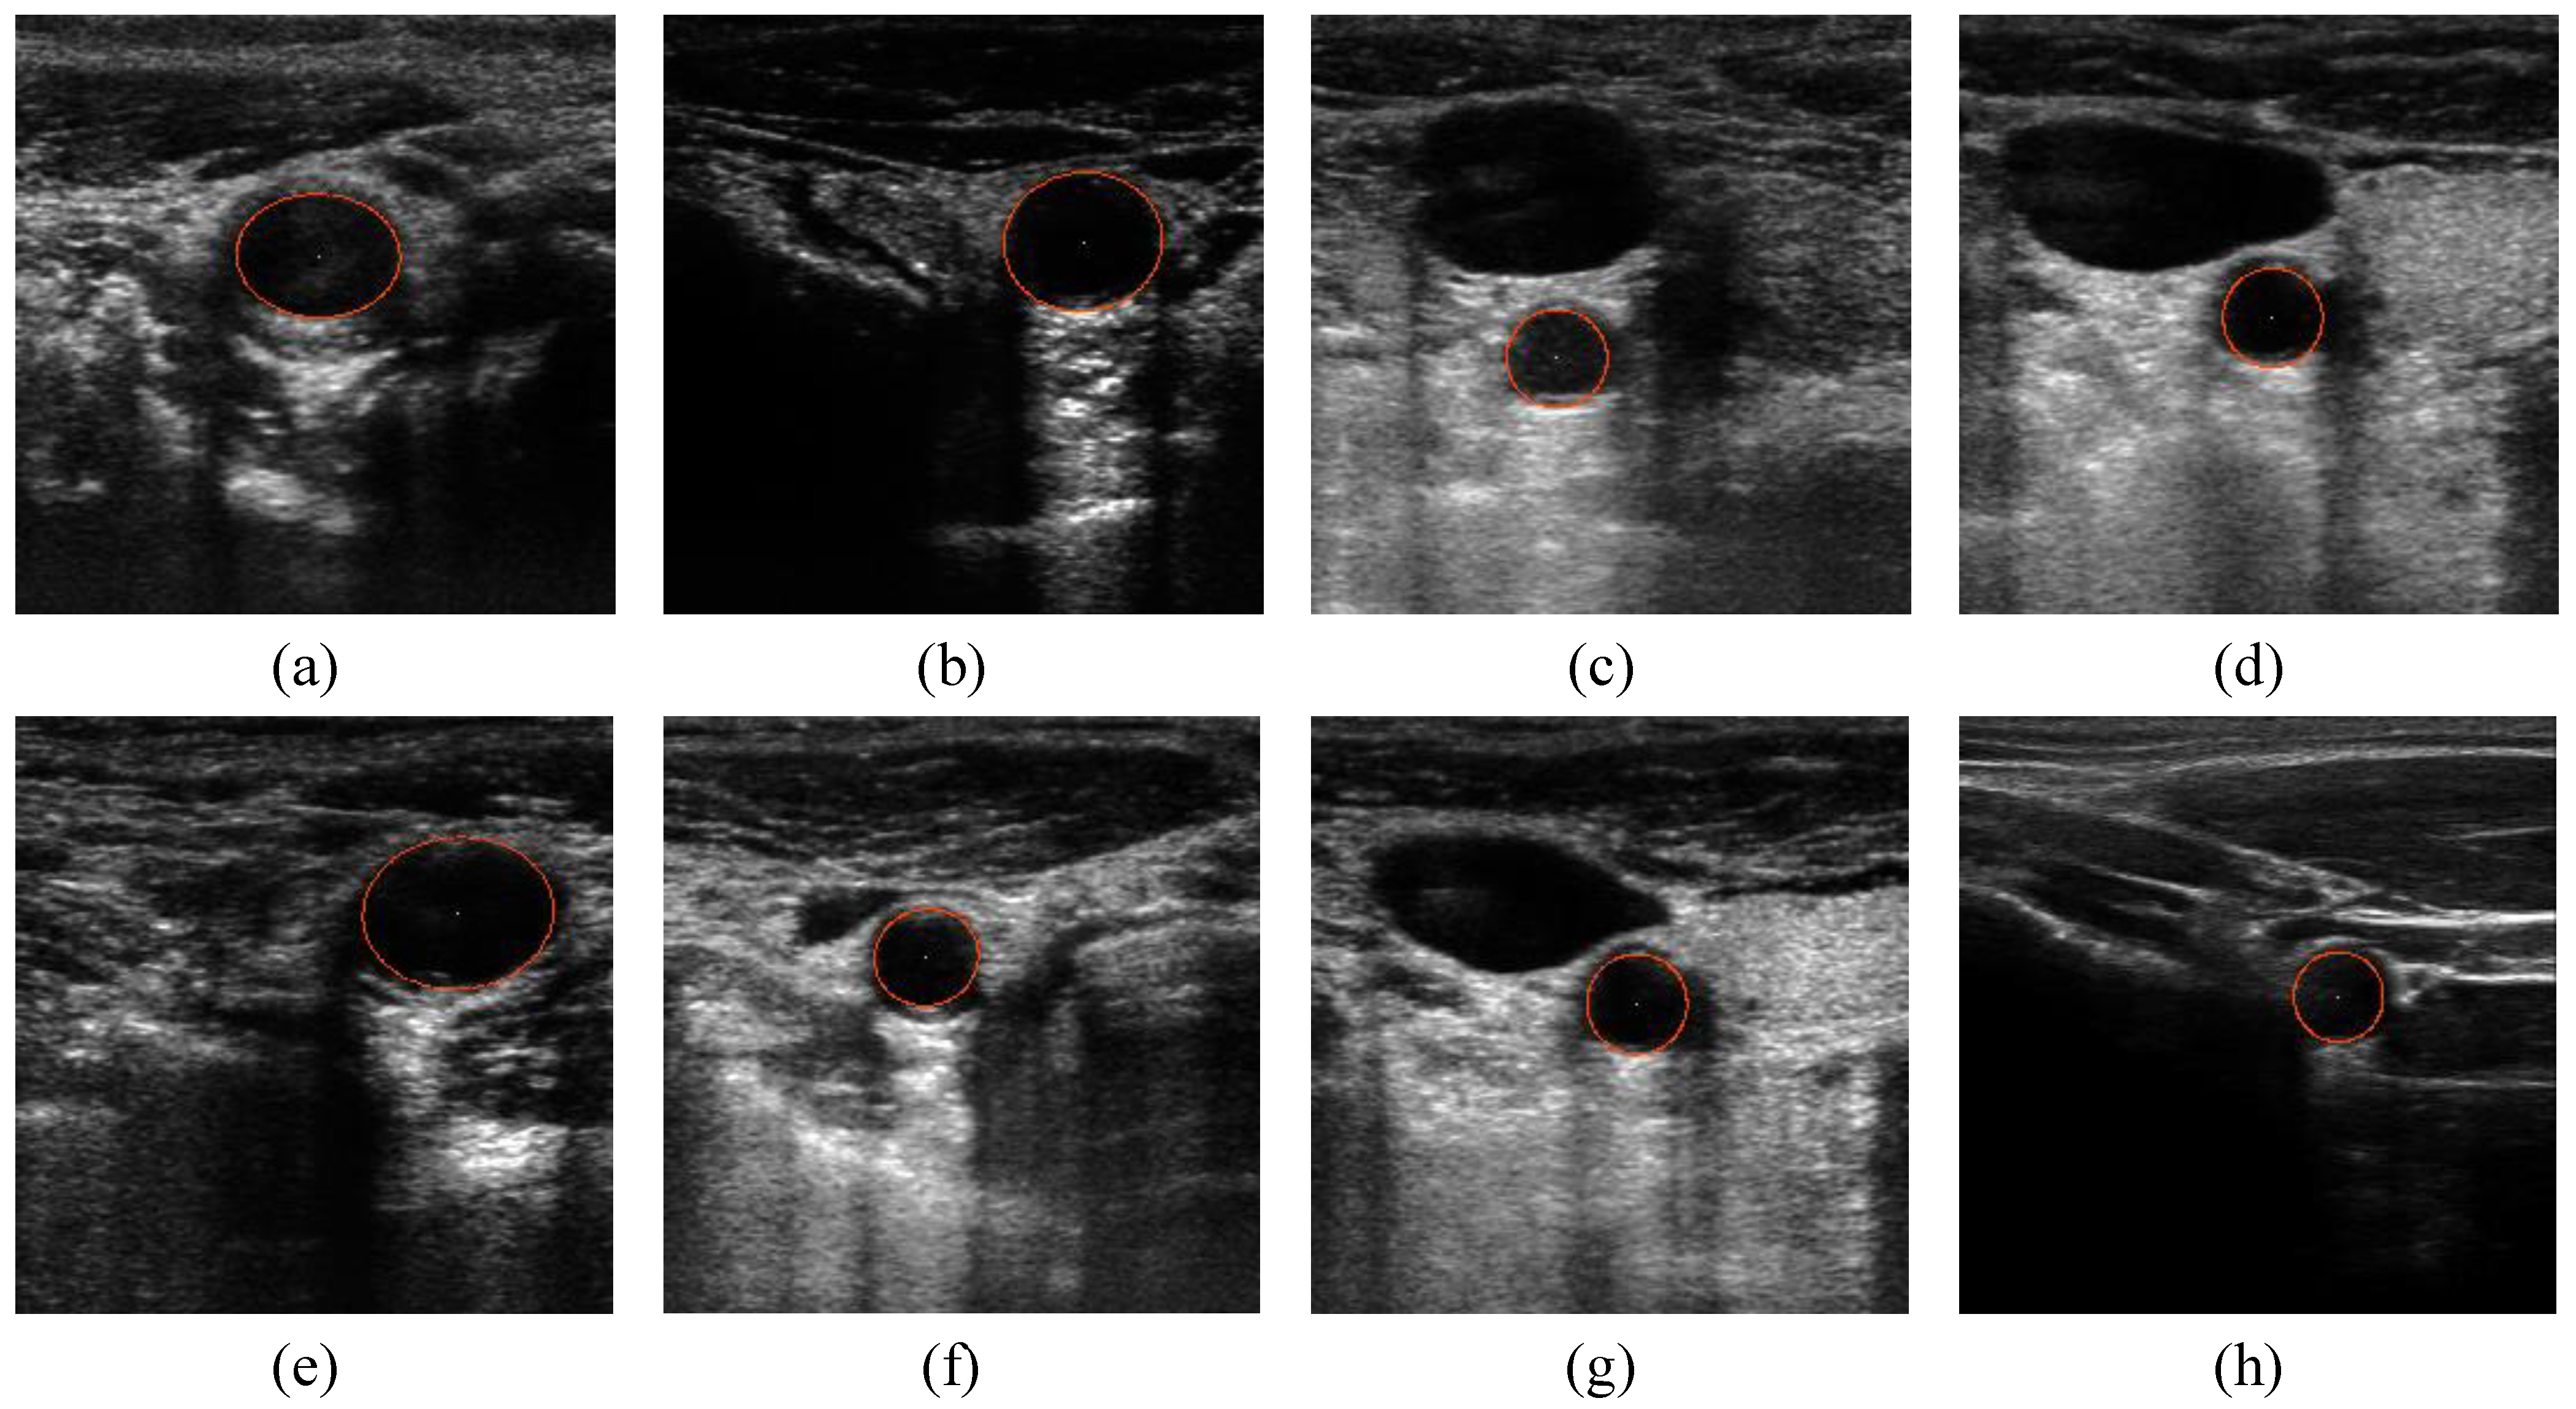

and  the random vectors in the evaluated generation. Figure 8 shows the obtained segmentation results with different mutation operators. To perform this test, the experiment has been repeated 10 times (per each operator) and the mean of the obtained results has been computed. It can be observed that the best mutation operation can have an impact of about 3% in precision and almost 1% in the F-measure with respect to the worst case.

the random vectors in the evaluated generation. Figure 8 shows the obtained segmentation results with different mutation operators. To perform this test, the experiment has been repeated 10 times (per each operator) and the mean of the obtained results has been computed. It can be observed that the best mutation operation can have an impact of about 3% in precision and almost 1% in the F-measure with respect to the worst case.